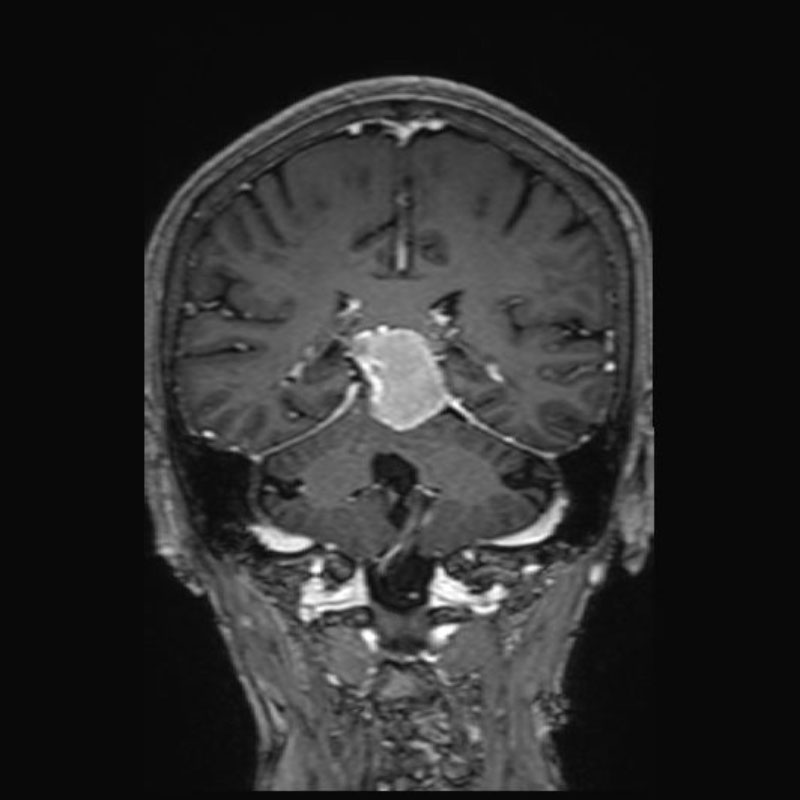

694

'25年11月

90代

頭蓋咽頭腫

頭蓋内腫瘍摘出術